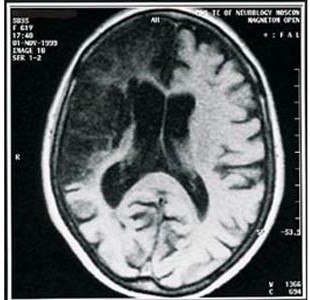

Обширный ишемический инсульт развивается вследствие полного прекращения кровоснабжения большого участка мозга, питаемого пострадавшим артериальным сосудом. При этом в этом участке мозга возникает отек. Зона ишемии, как правило, неоднородна. В этой зоне всегда есть нейроны, которые подвергаются обратимым изменениям. Именно на предотвращение гибели таких нейронов и направленно лечение. Если явления ишемии и гипоксии длятся долго, то мозговая ткань подвергается разрушению и наступает размягчение или инфаркт мозга. Последствия обширного ишемического инсульта могут привести к полной парализации больного с минимальной возможностью восстановления.